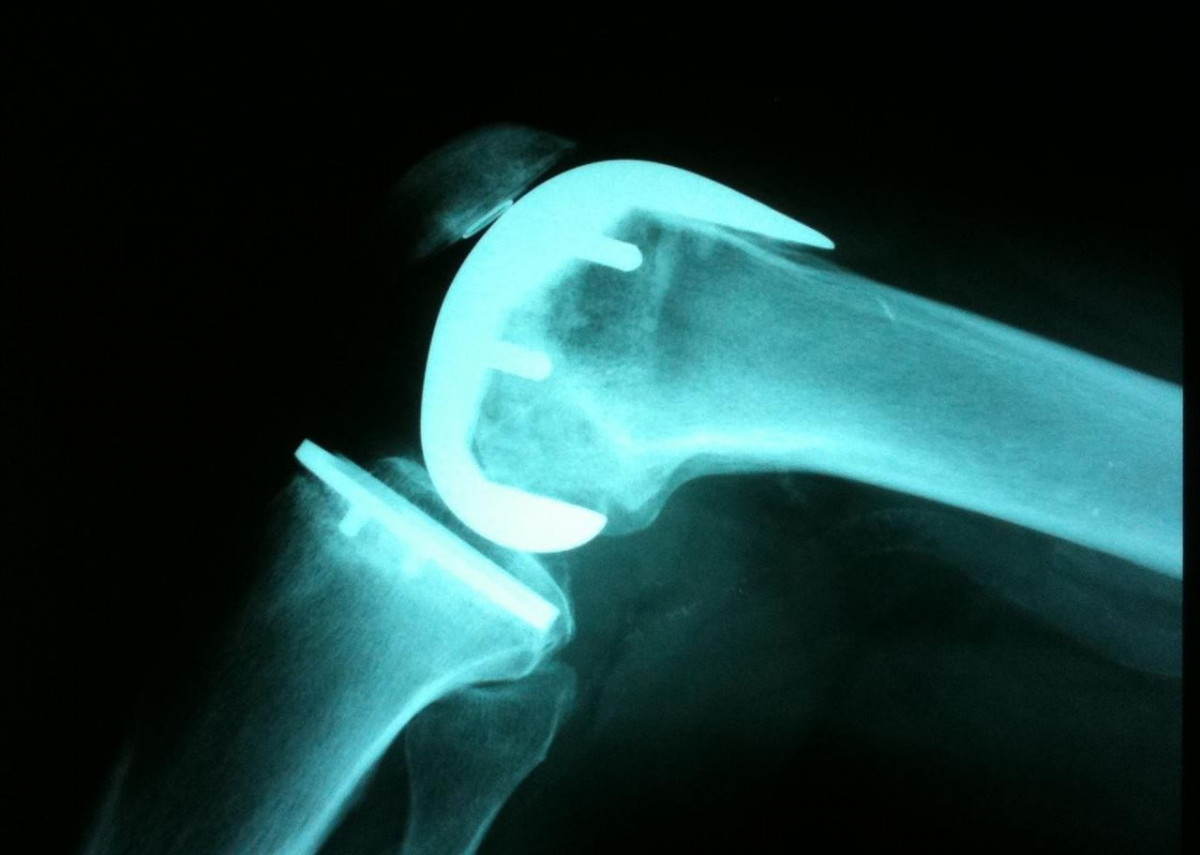

Catalunya Press.- Un total de 47 cirujanos ortopédicos están imputados en el 'caso Innova' de Reus, que investiga las presuntas irregularidades de las prótesis defectuosas de rodilla y cadera, principalmente de la empresa Traiber. Este centenar de especialistas médicos habrían cobrado comisiones ilegales de Traiber por colocar sus prótesis.